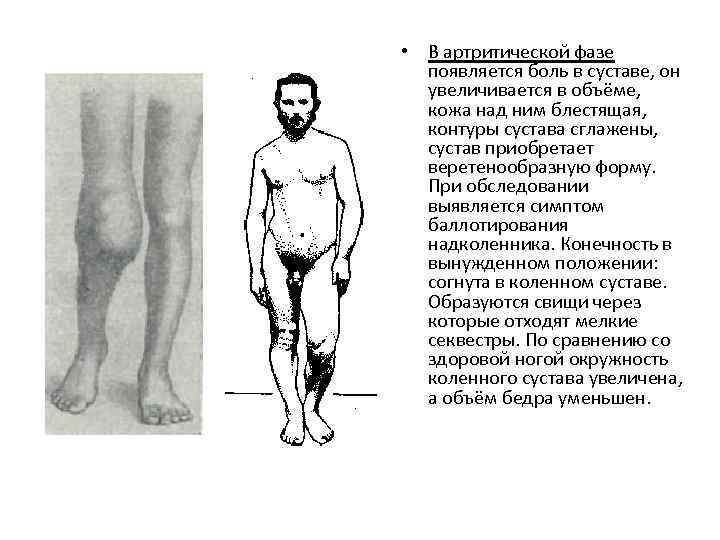

• В артритической фазе появляется боль в суставе, он увеличивается в объёме, кожа над ним блестящая, контуры сустава сглажены, сустав приобретает веретенообразную форму. При обследовании выявляется симптом баллотирования надколенника. Конечность в вынужденном положении: согнута в коленном суставе. Образуются свищи через которые отходят мелкие секвестры. По сравнению со здоровой ногой окружность коленного сустава увеличена, а объём бедра уменьшен.

• В артритической фазе появляется боль в суставе, он увеличивается в объёме, кожа над ним блестящая, контуры сустава сглажены, сустав приобретает веретенообразную форму. При обследовании выявляется симптом баллотирования надколенника. Конечность в вынужденном положении: согнута в коленном суставе. Образуются свищи через которые отходят мелкие секвестры. По сравнению со здоровой ногой окружность коленного сустава увеличена, а объём бедра уменьшен.